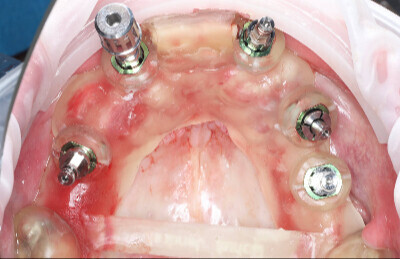

Navigovaná chirurgia, 5 implantátov

Autor práce Dr. Michal Repaši

Zubný technik Vasil Csopej

22. september 2021